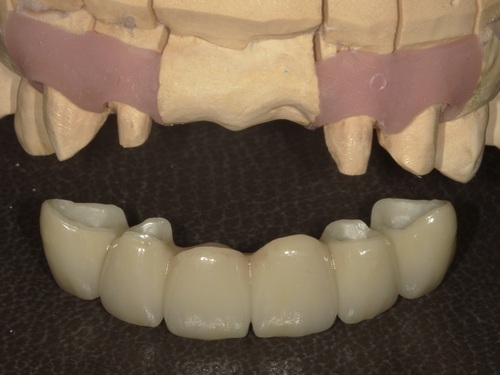

⑦セット

型取りから2週間ほどでジルコニアセラミックブリッジが完成してきました。

適合・色合い・噛み合わせに問題がないことを確認し、歯科用セメントでしっかりとセットしました。術前と比較して色も自然でとても美しい仕上がりかと思います。